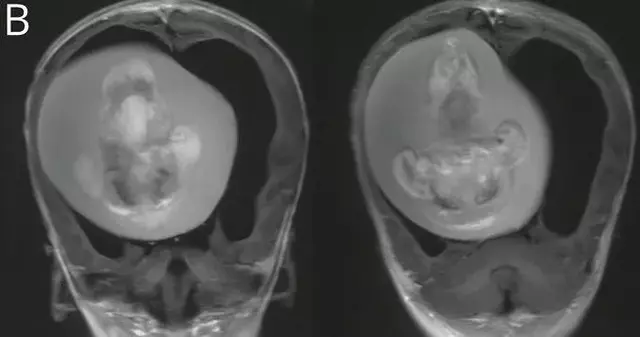

Vaka raporuna göre, araştırmacılar bebeğin kafatasını çeşitli görüntüleme yöntemleriyle incelediklerinde, beyninin sıkıştığını ve sıvı birikimi oluştuğunu tespit etti. Daha sonraki incelemeler ise, bebeğin aslında anne karnındayken bir ikiz kardeşi olduğunu, ancak ikinci bebeğin yeterince gelişemeyerek kardeşinin kafatasının içine sıkıştığını ortaya çıkardı. Doktorlar, fetüsün üst uzuvlarının, kemiklerinin ve hatta tırnaklarının geliştiğini, muhtemelen rahimdeki kardeşinin içindeyken aylarca büyümeye devam ettiğini bildirdi.

Yaklaşık 10 santimlik fetüs, ameliyatla çıkarıldı. Vaka, tıbbi literatürde sadece 18 kez rapor edilen bir durum olarak kayıtlara geçti. Bu olay, tıbbi dünyada oldukça nadir görülen bir fenomeni temsil ediyor. Benzer şekilde, 2015 yılında Çin'de bir erkek bebeğin testisinde doğmamış ikizinin fetüsü bulunmuştu. 20 günlük bebek, doğumun ardından testis torbasının şişmeye başlaması üzerine hastaneye kaldırılmıştı.